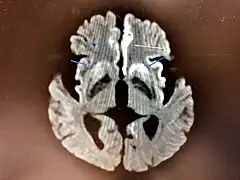

The symptoms of CJD are caused by the progressive death of the brain's nerve cells, which are associated with the build-up of abnormal prion proteins forming in the brain. When brain tissue from a person with CJD is examined under a microscope, many tiny holes can be seen where the nerve cells have died. Parts of the brain may resemble a sponge where the prions were infecting the areas of the brain.[17]

The classic histologic appearance is spongiform change in the gray matter: the presence of many round vacuoles from one to 50 micrometers in the neuropil, in all six cortical layers in the cerebral cortex or with diffuse involvement of the cerebellar molecular layer.[54] These vacuoles appear glassy or eosinophilic and may coalesce. Neuronal loss and gliosis are also seen.[55] Plaques of amyloid-like material can be seen in the neocortex in some cases of CJD.[56]